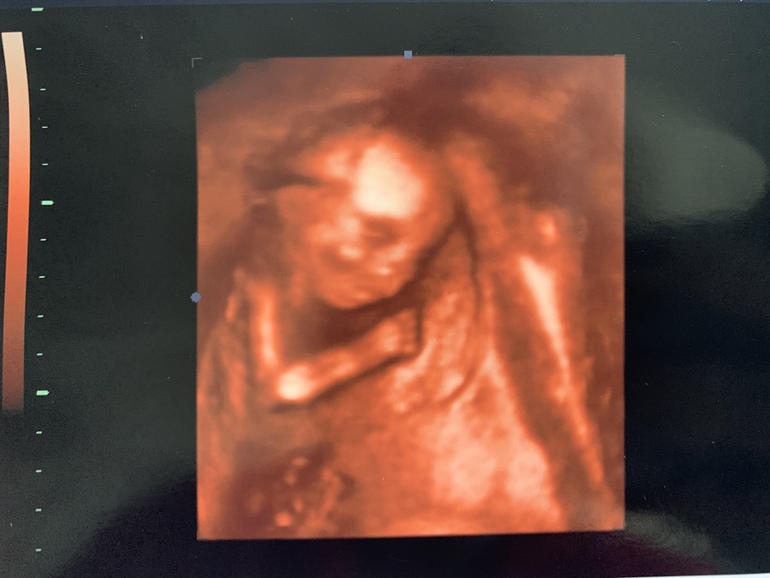

Наш 2 скрининг👶

Фотогалерея (Наши пузики и детки)Наш парень оказался на парнем,а милой девченкой😊весом 286 грамм.Всю ночь не спала перед узи ...очень волновалась.Успокоилась когда просмотрели уже все органы и сказали что все у нас хорошо.Теперь ждём 3 скрининга 👨👩👧

У нас сначала тоже такие интересные фотки получались ,просто два кулачка перед отцом о пол лба,я сначала немного растроилась,а потом проснулась и еле выловили личико.Из 6 фото что сделали вот эта единственная такая четкая с личиком

О, какая малышка😍 спит кажется ))